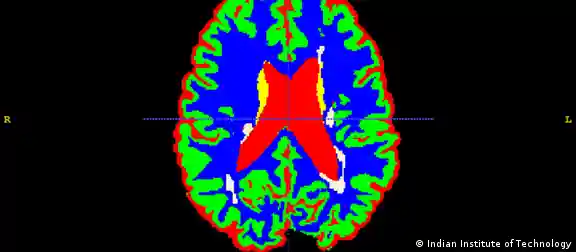

Indien Multiple Sklerose

صورة من: Indian Institute of Technology

التصلب المتعدد

التصلب المتعدد أو التصلب اللويحي هو مرض يصيب الجهاز العصبي للإنسان ويظهر فجأة. ويختلف تطور هذا المرض من مريض لآخر، فبينما يعيش مرضى معه دون أي أعراض تذكر، يضطر آخرون إلى اللجوء لكرسي متحرك بعد سنوات قليلة فقط.